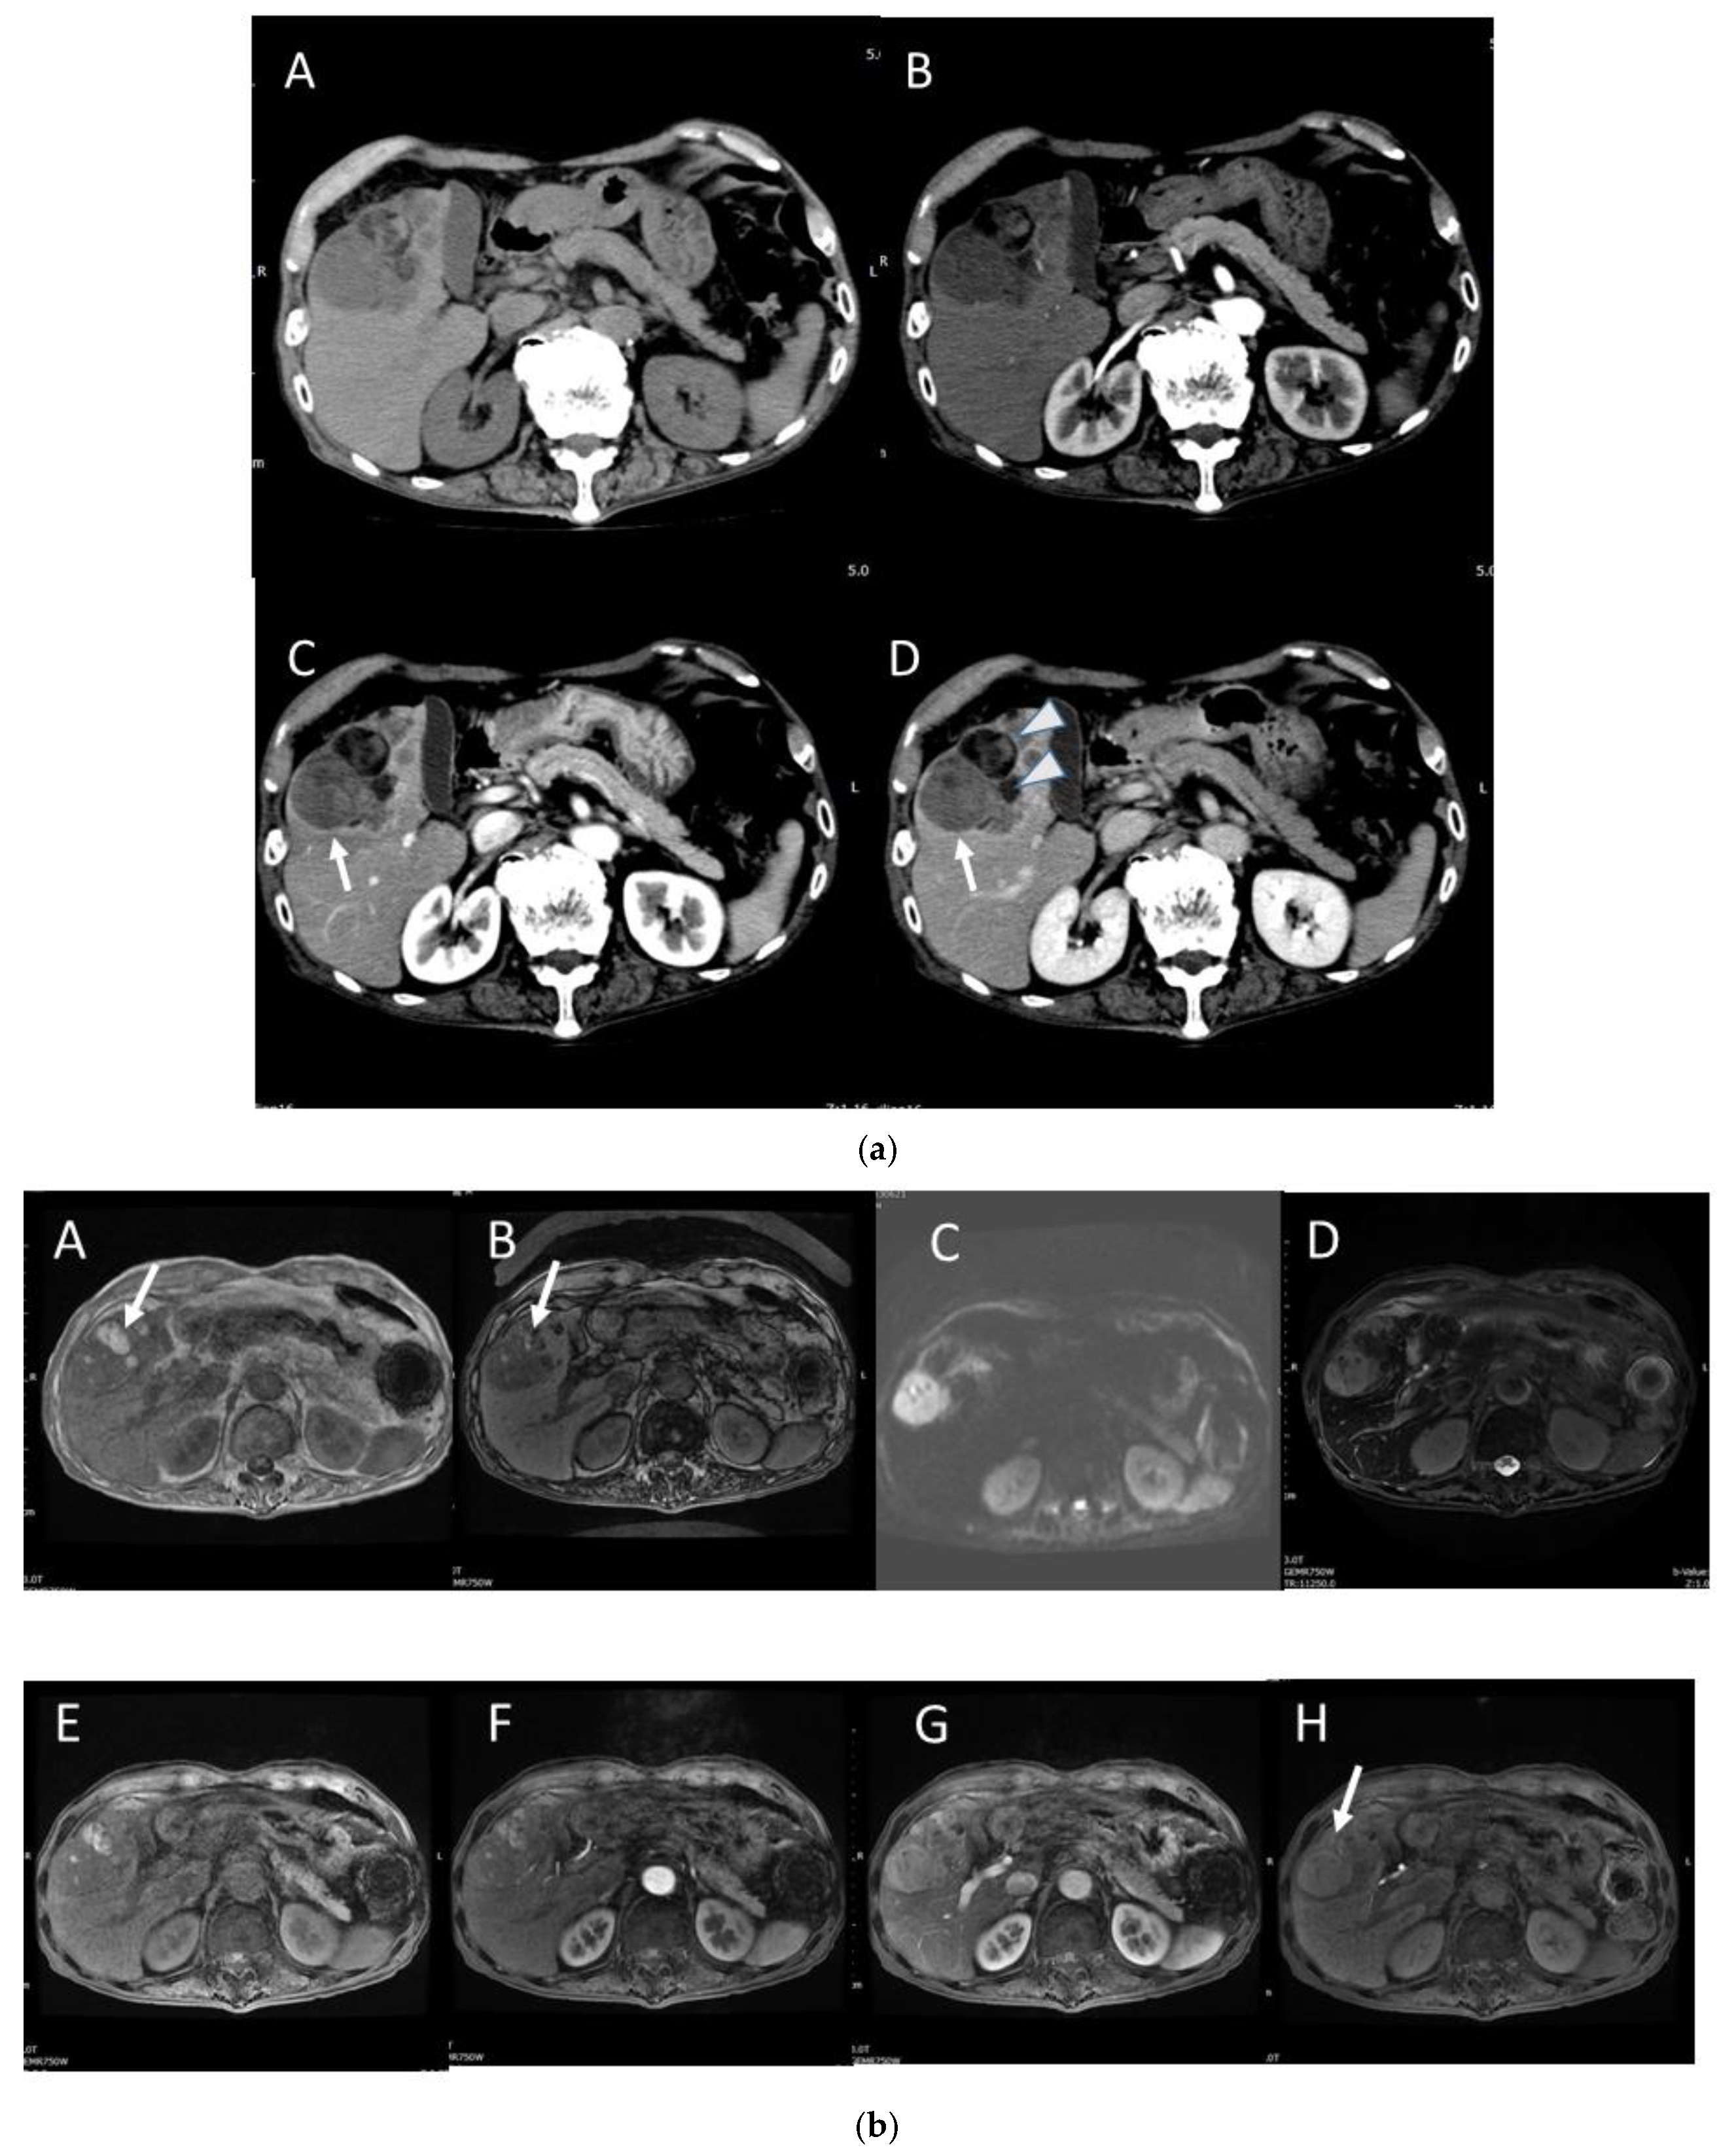

4.8. Steatohepatitic HCC (SH-HCC)